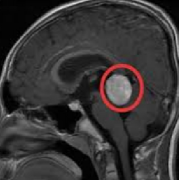

松果体囊肿是什么病?松果体囊肿是松果体的一种相对常见的良性疾病。松果体囊肿患者的临床治疗仍存在争议,是当患者出现非特异性症状时...

松果体区肿瘤 是指松果体内部或附近的异常生长。松果体是位于三脑室后大脑中线的一个松果体形状的小区域,它合成并分泌神经递质褪黑素,褪黑素在调...

松果体为长(5~8)mm、宽(3~5)mm的灰红色椭圆形小体,重(120~200)mg,几乎全部脊椎动物都拥有松果体。松果腺产生褪黑激素,一种5-羟色胺衍生的激素,可调...